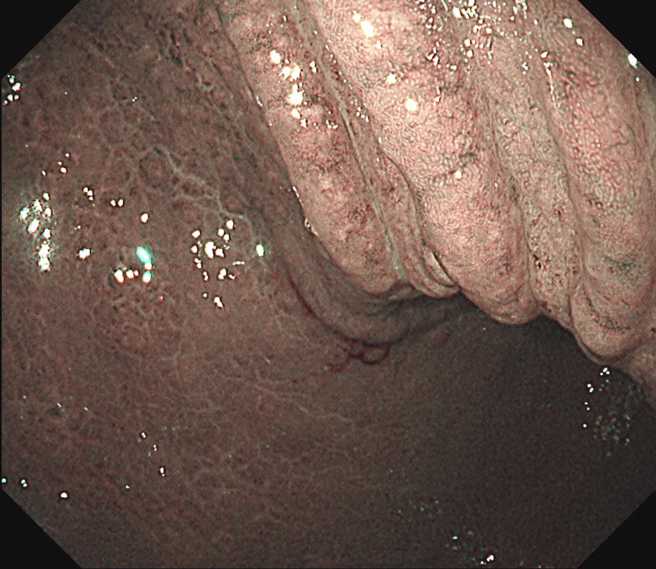

林相宏透过强化内视镜检查发现,对方胃表面黏膜已经出现不规则、类似龟裂的样子,经切片诊断结果证实,是罹患了低恶性度的淋巴瘤「胃淋巴癌(MALToma)」。

医师林相宏透过强化内视镜检查发现,对方胃表面黏膜已经出现不规则、类似龟裂的样子。(图/翻摄自脸书粉专胰臟医师林相宏)